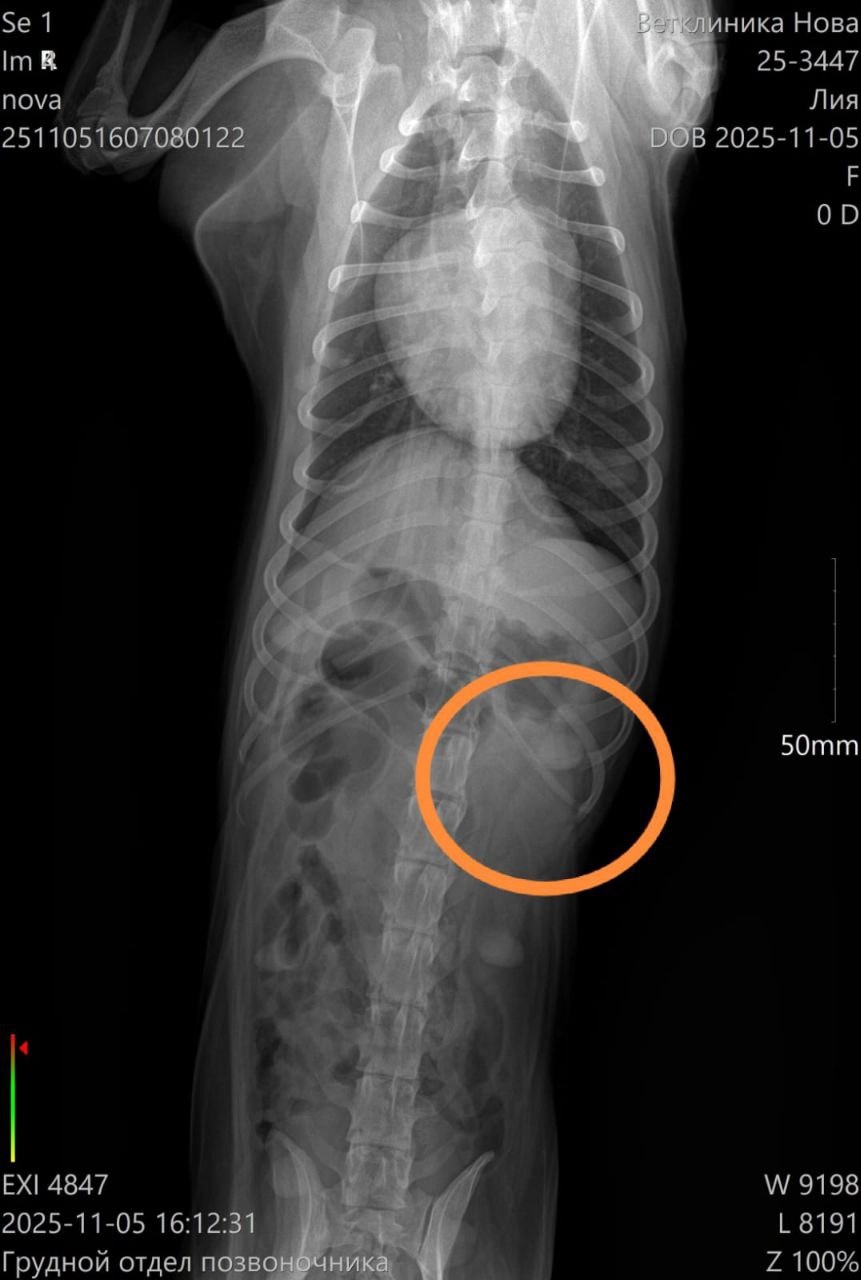

Девчонка не встает на задние лапы,чувствительности нет. Сделали рентген,по снимку у Леи сломано ребро(травма старая,органы не задевает,поэтому трогать ее не нужно.)

🙏Явно что-то с позвоночником,но без МРТ просто по рентгену врач не видит,что с ним.